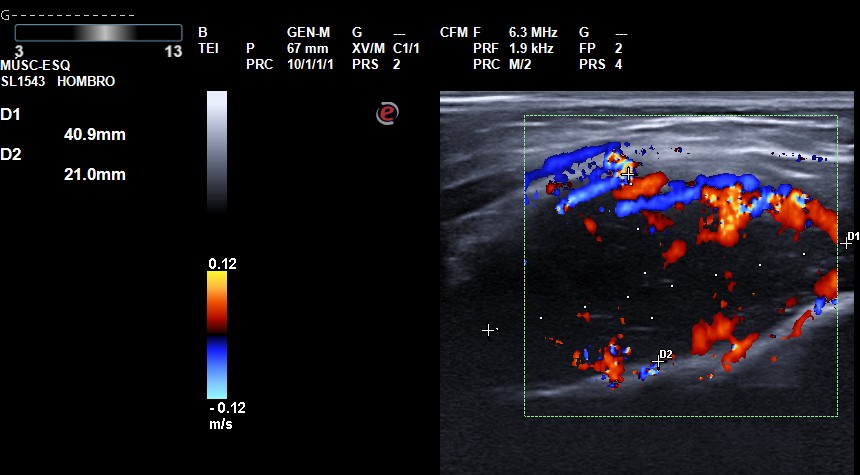

Una mujer de 19 años tenía tumoración blanda en húmero distal derecho. Realizamos una ecografía que mostró una lesión ubicada entre cortical humeral y braquial, hipoecoica, de contornos bien definidos, sin refuerzo posterior con captación Doppler. La RMN evidenció tumor mesenquimal con remodelación ósea, derivándose urgentemente al circuito de tumores músculo-esqueléticos.